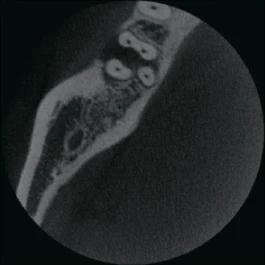

Изображения с высоким разрешением для точной диагностики

Получите исключительную чёткость изображения и настраиваемый объём сканирования с помощью RAYSCAN. Адаптируйте свои снимки в соответствии с вашими конкретными клиническими потребностями, и будьте уверены в том, что запечатлеете каждую сложную деталь и раскроете безграничные возможности.

FOV 10×10 см, 160 μm

FOV 4×5 см, 70 μm